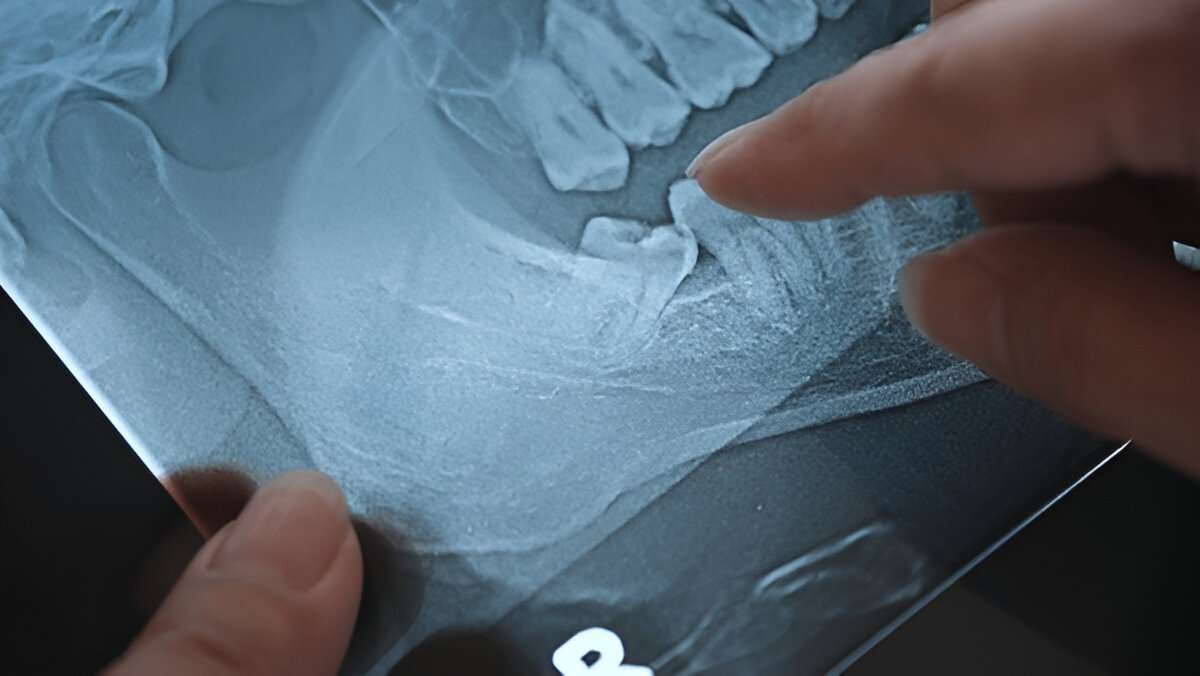

Impacted wisdom teeth

Wisdom teeth can cause more than just discomfort. These third molars often emerge in late teens or early twenties. When they don’t have enough room to grow properly, they become impacted wisdom teeth. This condition can trigger swelling, soreness, and even infection. Many people ignore the pain, thinking it will pass, but unaddressed issues can worsen over time. Understanding the root cause of wisdom teeth pain is the first step toward effective treatment.

Not all wisdom teeth cause pain, but proper evaluation is crucial. X-rays reveal whether teeth are impacted or likely to create problems in the future. Your dentist will discuss options for pain management and, if necessary, surgical removal. Understanding the procedure in advance helps patients feel in control. Preparation and clear communication with a dentist or oral surgeon often lead to smoother experiences.